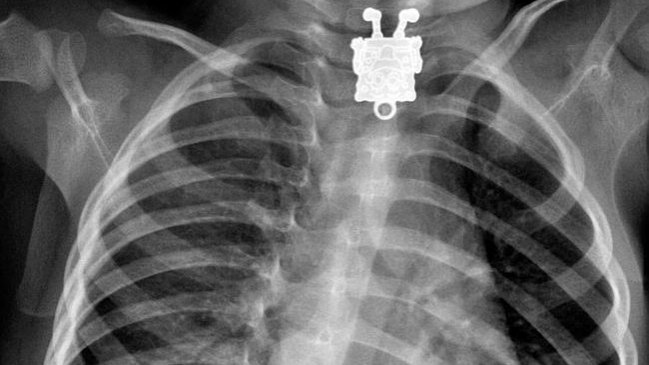

Cientos de objetos fueron introducidos por los estadounidenses en sus cuerpos durante 2017 y el portal Deadspin recopiló una lista con los elementos más extraños que las personas no pudieron sacar de sus orificios por lo que recurrieron a salas de emergencia.

El listado fue elaborado sacando los datos de los registros públicos de las visitas a urgencias en el país, publicadas por la Comisión para la Seguridad de los Productos de Consumo de Estados Unidos (NEISS).

Allí se detallan las cosas por cada parte del cuerpo y destaca la preocupante cantidad de objetos que las personas ingresaron a través de sus rectos.